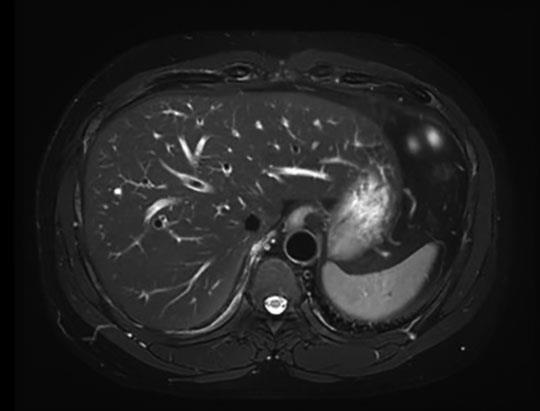

Large FOV Abdominal Imaging

Free-breathing Abdominal Imaging with EasySense